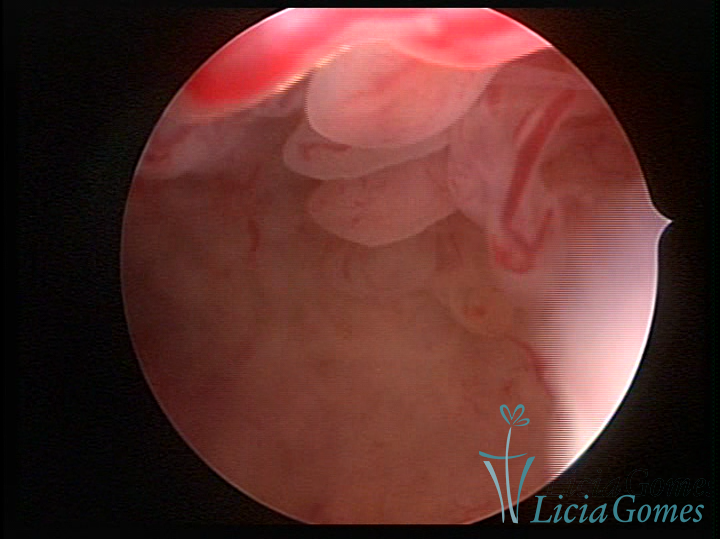

Este pode apresentar uma gama variável de aspectos macroscópicos, com aspecto pseudopolipoide; lembrando tecido cerebroide ou com reação deciduoide;a vascularização superficial é mais evidente e com vasos em formatos de saca-rolha ou espirais visualizando também a vascularização com atípias, com aumento do calibre dos vasos superficiais, pode ser encontrado também tecido em necrose, poderá haver um pequenos dendritos (papilomatoso).